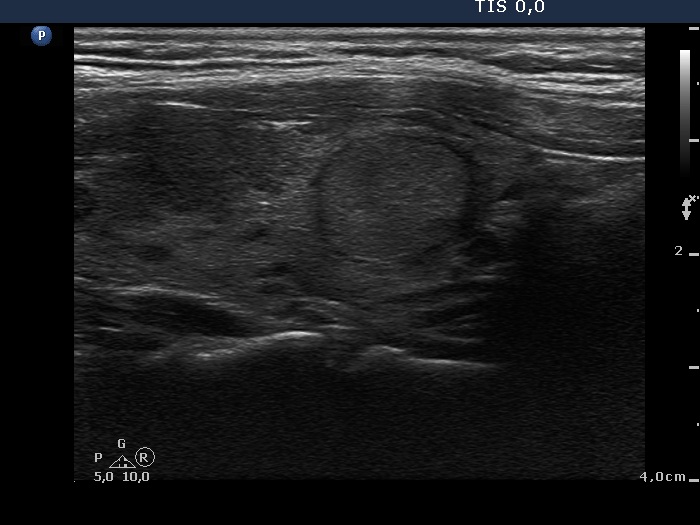

Discrete lesion or nodule in Hashimoto's thyroiditis - case 10 (95) (ultrasonographic picture 8)

Left lobe, another longitudinal view.